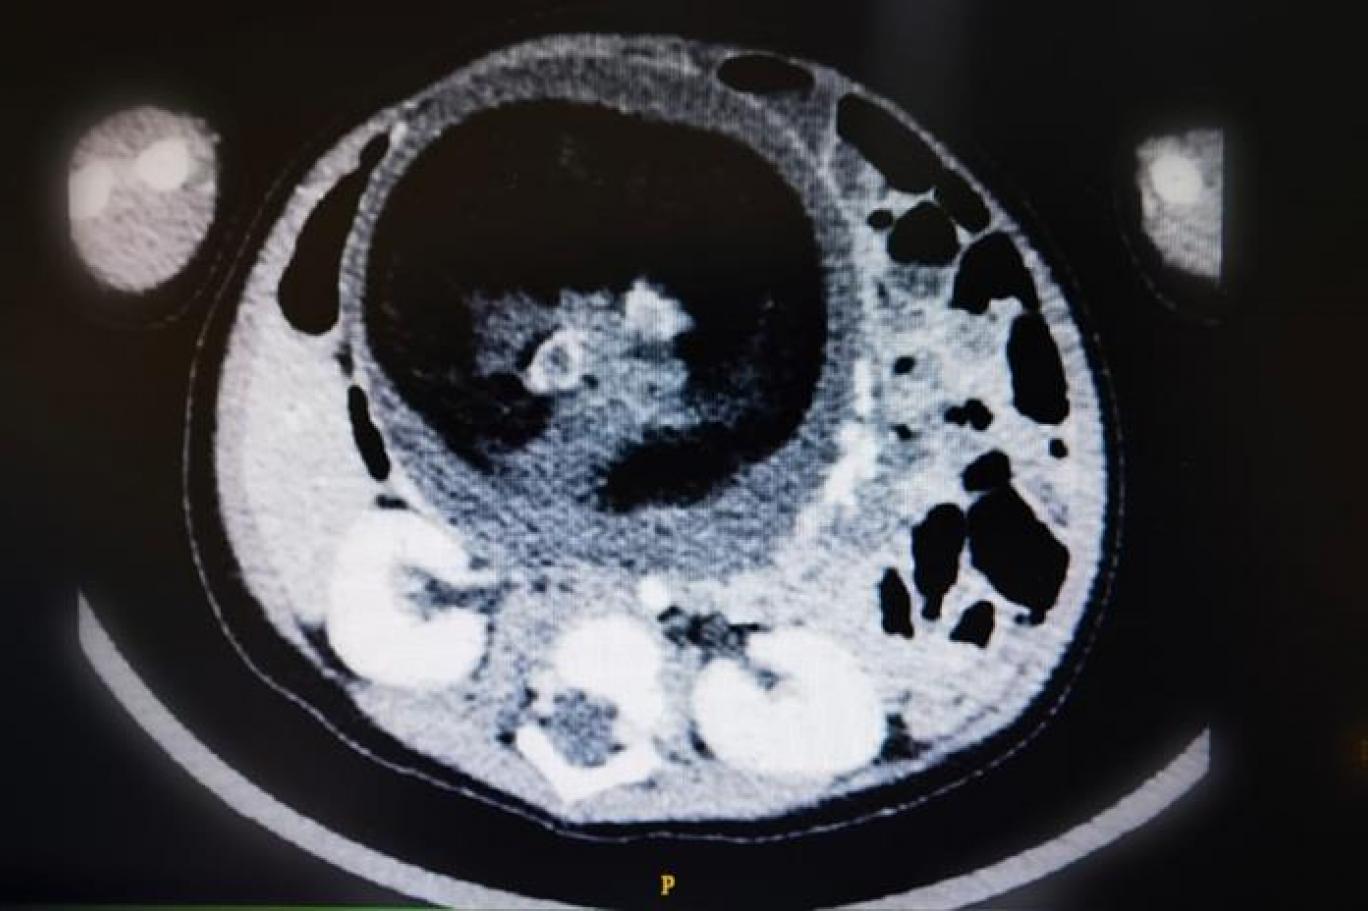

صورة مقطعية للحالة النادرة التي يظهر فيها جنين داخل جنين قبل الولادة (وكالة الأنباء العمانية)

في حالة طبية جراحية نادرة على مستوى العالم، تمكن قسم جراحة الأطفال بالمستشفى السلطاني بعُمان، من إجراء جراحة نادرة، تمثلت في استئصال جنين من داخل جنين، لطفل يبلغ من العمر ثمانية أشهر، سُمح له بمغادرة المستشفى بعد ثلاثة أيام من إجراء الجراحة، والتحقق من الفحوص والمؤشرات التي أثبتت نجاح العملية، على الرغم من الظروف الاستثنائية للحالة.

وتوصف الحالة طبياً بأنها عيب خُلقي تتكون فيه كتلة من الأنسجة تشبه الجنين داخل الجسم، وهناك نوعان من نظريات المنشأ في شأن الحالة، إحداها تعتبر أن الكتلة تبدأ كجنين طبيعي، ولكنها تتحول إلى مغلف داخل توءمه، والأخرى تعتبر أن الكتلة هي ورم مسخي متطور للغاية، ويحدث بنسبة واحد لكل 500 ألف ولادة حية.